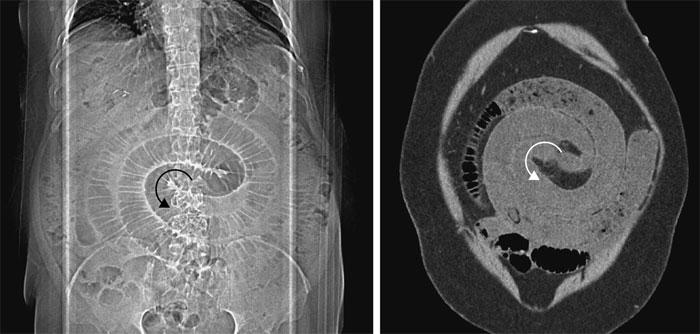

Обследование кишечника. Фото: nejm.org